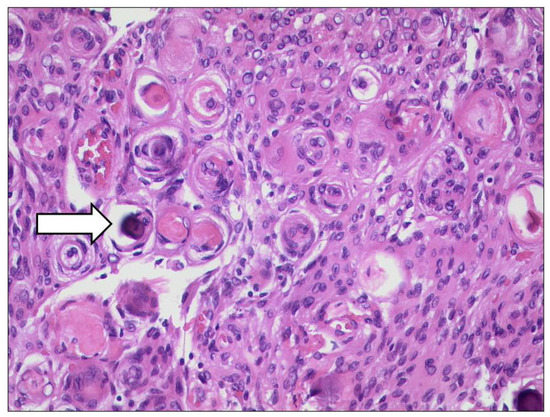

3.6.2. Rhabdomyosarcoma